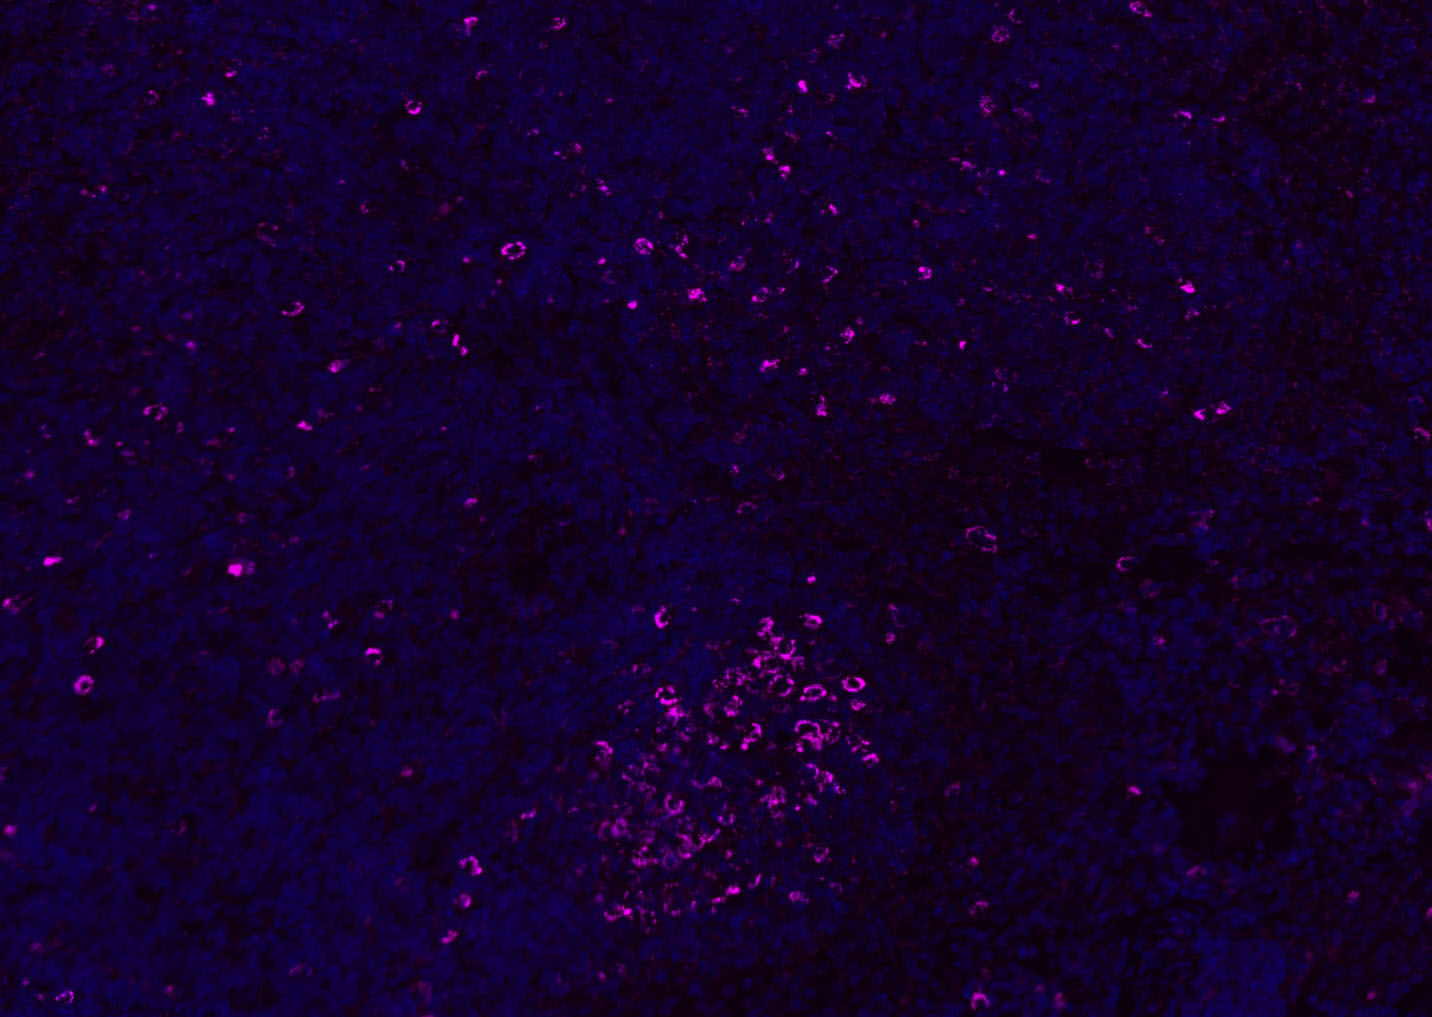

Paraformaldehyde-fixed, paraffin embedded (mouse thymus); Antigen retrieval by boiling in sodium citrate buffer (pH6.0) for 15min; Blocking buffer (normal goat serum) at 37°C for 30min; Antibody incubation with (CD8B) Polyclonal Antibody, Unconjugated (bs-4914R) at 1:200 overnight at 4°C, followed by a conjugated Goat Anti-Rabbit IgG antibody (bs-0295G-AF488) for 90 minutes, and DAPI for nuclei staining.